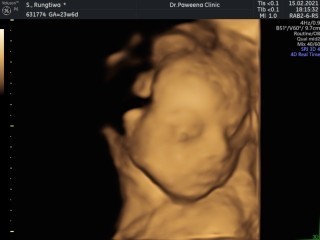

ขอดูแม่ๆทีม มิ.ย 64หน่อยจ้า บ้านนี้ยังไม่รู้เพศเลยค่ะ แม่ๆคิดว่าเพศไหนคะ 26w6d #ขอบคุณสำหรับคำตอบค่ะ #ท้องแรกค่ะ